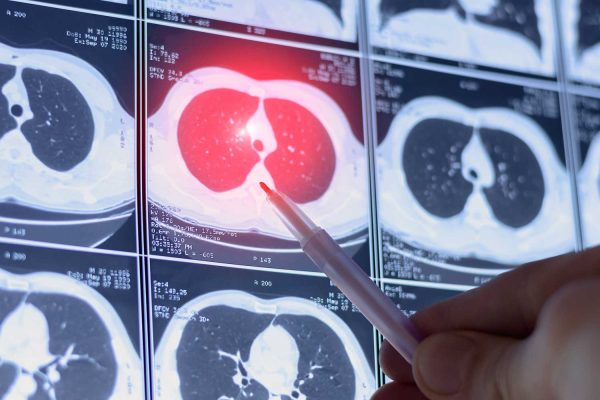

What Is a CT Scan? How It Works, What It Shows, and What to Expect

A CT scan is a powerful medical imaging test that helps doctors see detailed pictures of the inside of your body. At IPMC in Northeast Philadelphia, we offer advanced CT imaging in a comfortable outpatient setting so you can get answers quickly without the stress of a hospital visit.